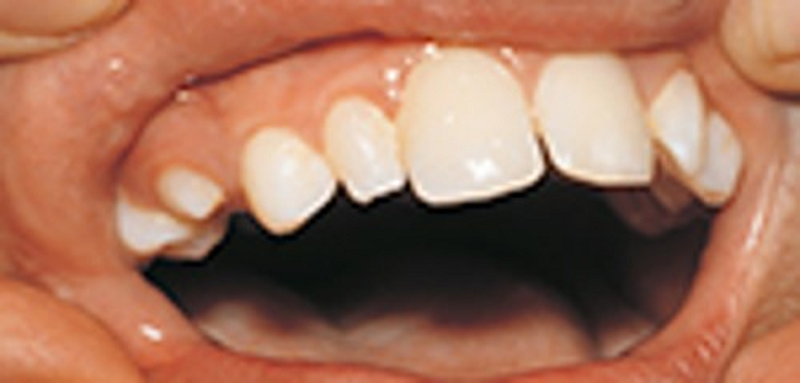

{"name":"Oral Path ID Chapter 6-9", "url":"https://www.quiz-maker.com/QPREVIEW","txt":"This condition is linked with Keratinosis of the palms of the hands & the soles of the feet. Individuals with this condition are likely to experience tooth mobility and premature tooth loss., This Term is used to describe The Appearance of type III (hypomaturation) Amelogenesis Imperfecta, Radiographs of a person with this condition appear to have a multilocular or “soap bubble” appearance","img":"https://www.quiz-maker.com/3012/CDN/92-4508546/final-pic-1.png?sz=1200"}